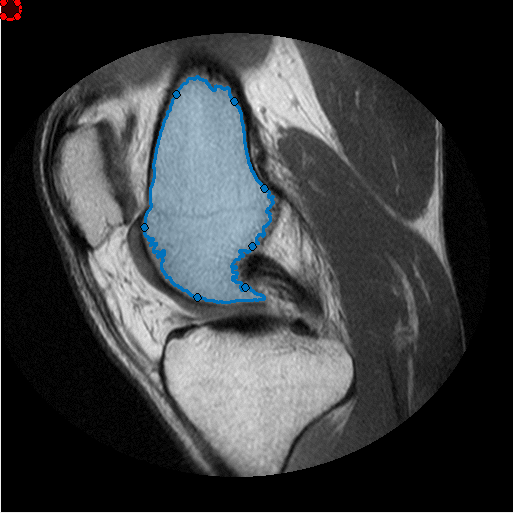

Создайте Круговой ROI, который будет использоваться в качестве средства стирания или инструмента редактирования ROI кисти. (Можно использовать любой images.roi.* классы путем создания небольшого изменения, упомянутого ниже).

he = images.roi.Circle(... 'Center', [50 50],... 'Radius', 10,... 'Parent', gca,... 'Color','r');

Сопоставьте два прослушивателя события с Круговым ROI. Каждый слушает для перемещения ROI, и другой слушает для того, когда перемещение останавливается. ROI, перемещающий функцию обратного вызова, пример убеждается, что имел свою привязку положения к пиксельным местоположениям и также изменил цвет (Красный/Зеленый), чтобы указать, удалит ли операция редактирования или добавит к целевому ROI от руки. Если ROI редактора прекращает перемещаться, мы создадим соответствующие бинарные маски для ROI редактора и целевого ROI от руки и сделаем необходимое редактирование. Наконец, мы преобразуем обновленную маску назад к объекту ROI от руки. Обеспечьте электричеством прослушиватель, чтобы реагировать каждый раз, когда этот ROI редактора перемещен

Это - ROI, перемещающий функцию обратного вызова. Эта функция гарантирует, что привязки ROI редактора к пиксельной сетке, и изменяют цвет ROI редактора, чтобы указать, добавит ли это к ROI от руки или удалять область от ROI от руки. Если центр ROI редактора находится вне целевого ROI от руки, удаляет операцию, в противном случае это 'добавит'.